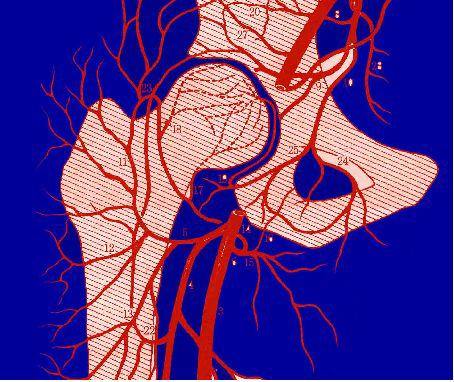

成年人早期股骨头坏死

股骨头坏死(nosteonecrosis of femoral head)是由各种病因引起股骨头血液供应破坏而引起软骨下骨变性、坏死,造成股骨头塌陷,最终导致髋关节退行性破坏。ESWT 可以治疗成年人早期股骨头缺血坏死,延缓股骨头坏死的进展,其疗效与钻孔减压类似。